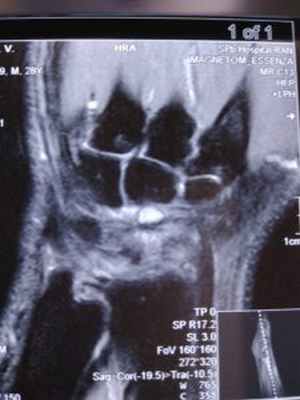

Для диагностики заболевания часто достаточно осмотра врача, однако для уточнения иногда используют УЗИ или МРТ (рентгенография в данном случае не информативна).

В редких случаях может быть использована МРТ, особенно для поиска очень маленьких гигром на тыле запястья и дифференциальной диагностики с болезнью Кинбека.